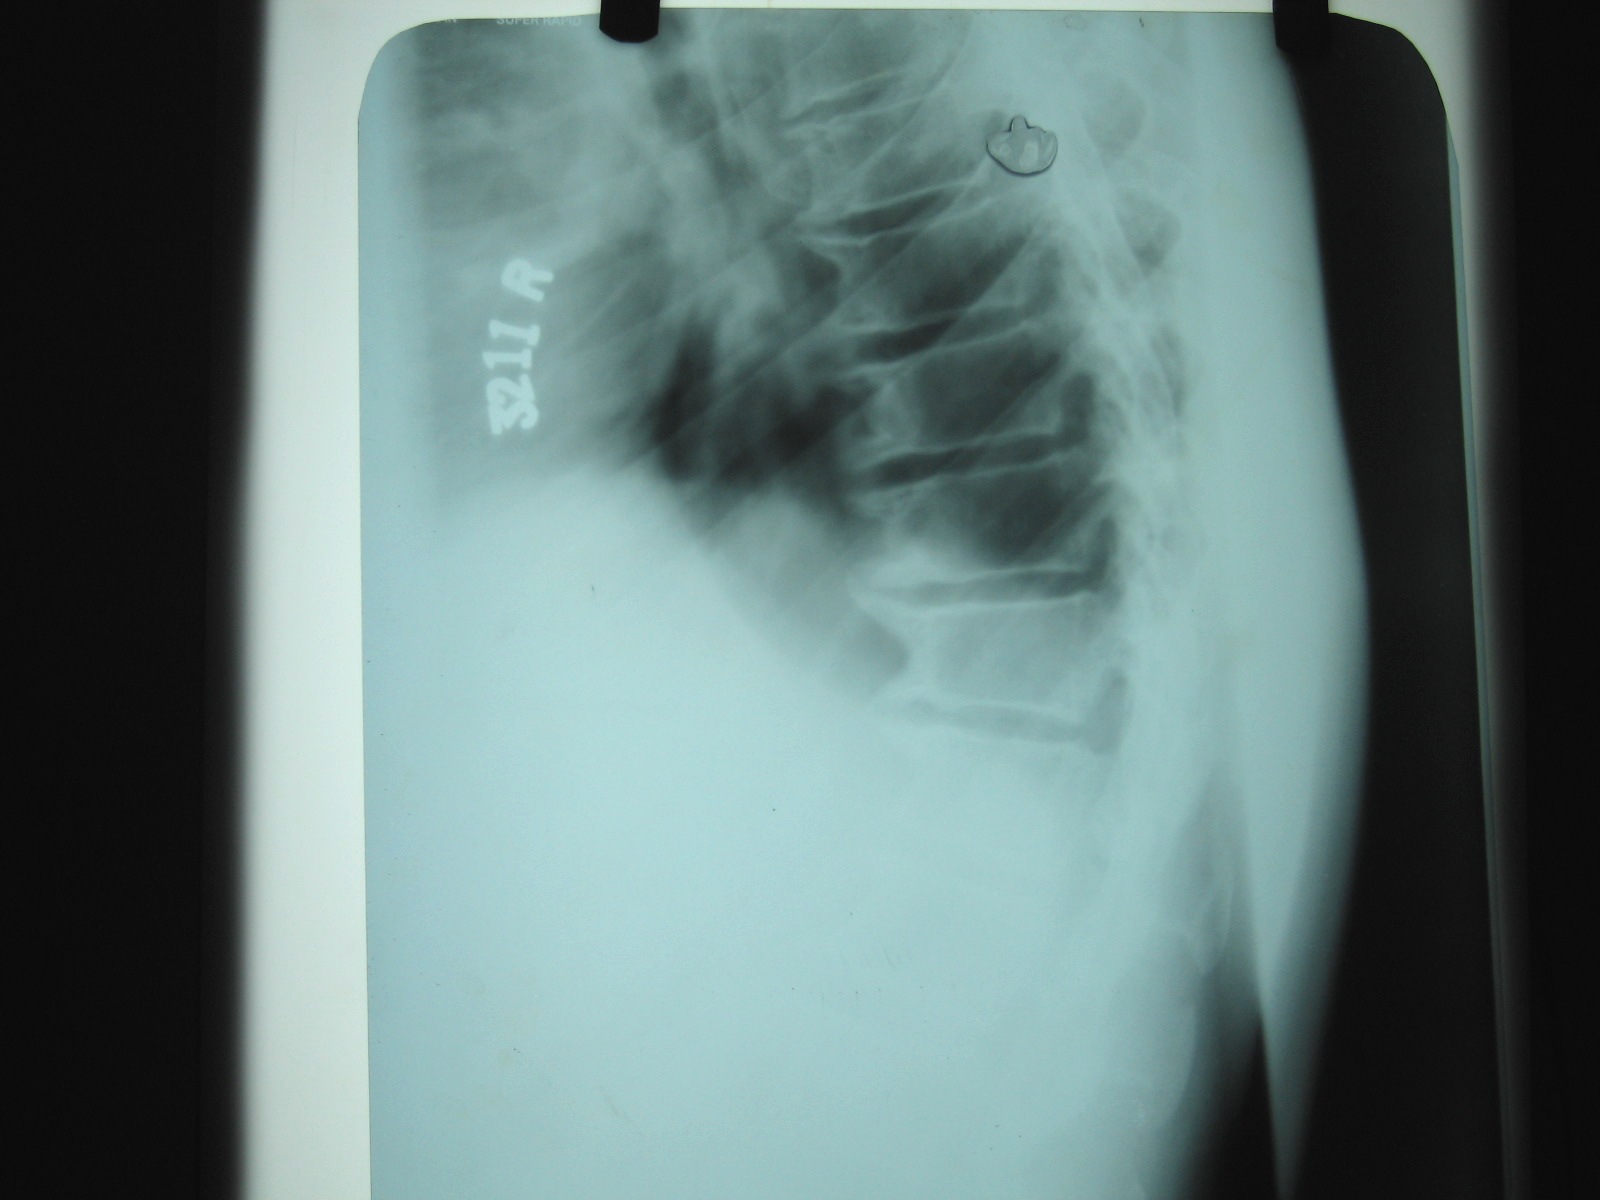

Fig.5 T.L spine lateral view-different patient